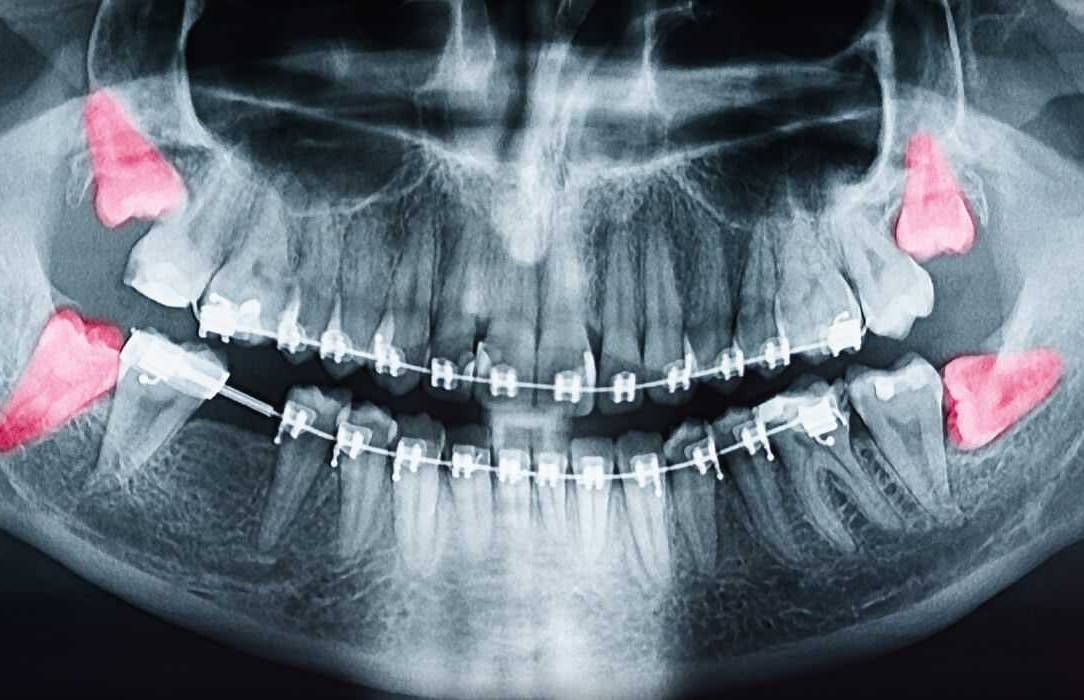

Tooth Extractions

Wisdom tooth extractions are a fairly common procedure. Wisdom teeth often cause problems as they are trying to protrude through the gums. When a wisdom tooth is impacted, it means the tooth is coming in at an angle and not straight through the gum line.